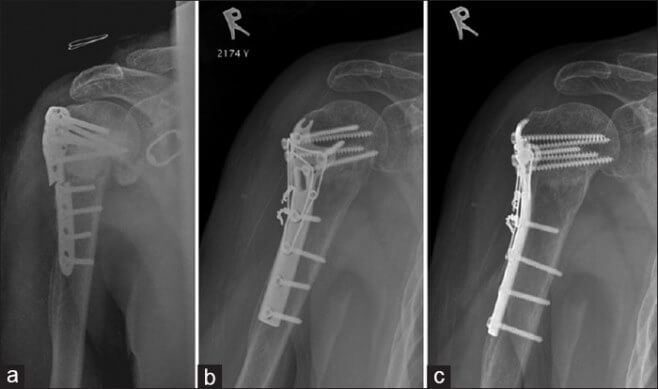

Для фиксации фрагментов применяют накостный остеосинтез или чрезкожную компрессию с помощью аппарата Илизарова. При отрыве большого бугорка используется фиксация шурупом или проволокой.

Во время операции разрез выполняется от акромиально-ключичного сустава вдоль дельтовидно-грудной борозды вниз к большой грудной мышце. Чаще всего применяют погружной остеосинтез с винтами, Т-образными и угловыми пластинами, а также фиксаторами с термомеханической памятью формы.

В старческом возрасте оскольчатые переломы срастаются хуже из-за недостаточного кровоснабжения. Иногда выбирают эндопротезирование вместо остеосинтеза, если операция возможна. Остеопороз является противопоказанием. При хирургическом вмешательстве применяют малоинвазивные техники и фиксаторы, которые минимально травмируют мягкие ткани и кости. Фиксацию пластиной в пожилом возрасте планируют с учетом ее длительного пребывания в кости.

После хирургического восстановления плечо фиксируют лонгетой. С третьего дня после репозиции и фиксации пациенту рекомендуют шевелить пальцами, сгибать и разгибать лучезапястный и локтевой суставы. Операционные швы снимают через неделю. Движения в плече разрешены с 20-го дня. Металлические элементы при остеосинтезе удаляют через три месяца.